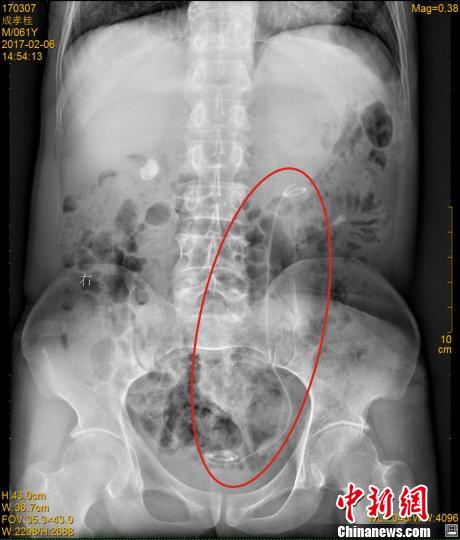

在医院接受B超检查时,医生发现成先生双肾均有结石、严重积水,此外,其左侧腰部还有一根条状物。在拍摄了X光片后,医生才发现,成先生体内竟然遗留着一根医用导管(双J管)。医生仔细询问后,成先生终于想起自己7年前接受过手术,这意味着这根长达30多厘米的导管,在其体内隐藏了7年时间。

2月9日,窦医平医生小心翼翼地从成先生体内取出了这根双J管。取出的双J管上,附着很多结石沉渣,原本白色的导管已变成黑色。取出导管后,医生又将其左肾中约1.5x1厘米大小的结石粉碎取出,然后重新置入了一根全新的导管。